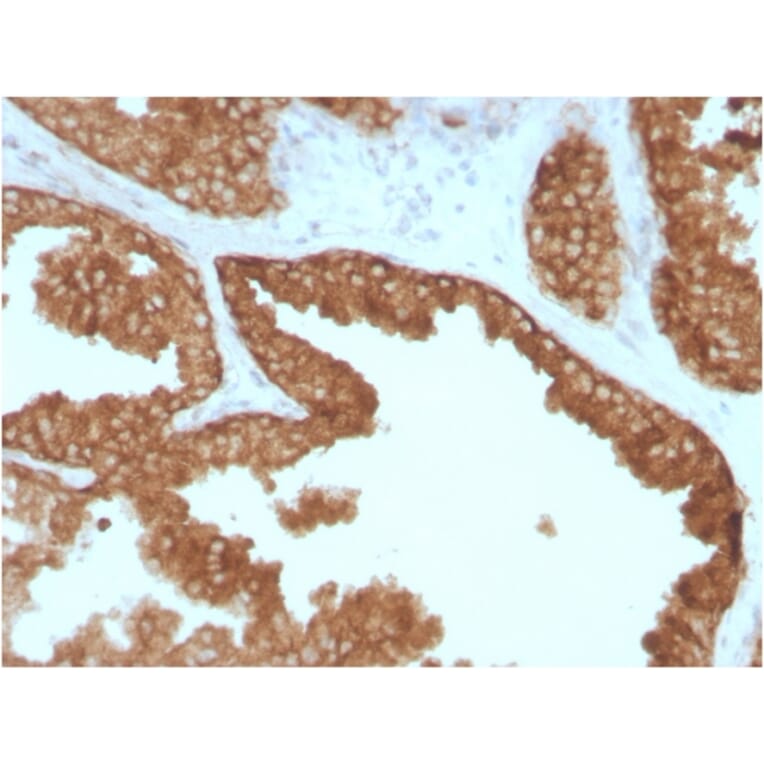

Anti-RET Antibody [RET/2795] - BSA and Azide free (A253062)

Mouse monoclonal [RET/2795] antibody to RET for IHC-P.

Mouse monoclonal [RET/2795] antibody to RET.

IHC-P

IHC-P: 1-2 µg/ml